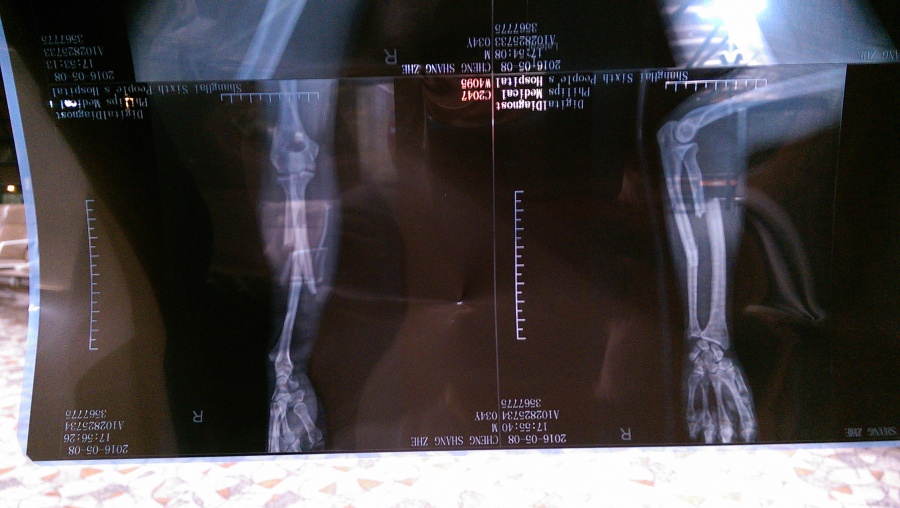

開放自由練習後,到下午約四點半,阿哲跳一個高度不高的檯子,但由於落地的角度不佳,手就摔斷了。當時大會很快就叫了救護車,在場也剛好還有醫護人員到場簡易的協助,我們在大約五點初頭就一起將阿哲送到了上海人民第六醫院。

後來與醫生討論過後,選擇有二,一是留在上海這家醫院開刀治療,二是上石膏回台灣治療。但因為選擇一必須要等到兩天後才有機會開刀,而開刀後也不見得能馬上離開醫院,於是我們就選擇回台治療,現在想起來,這確實是最佳的做法。

我們順利的搭上飛機,返抵桃園機場,被接駁到停車處後,我就開車直接送他前往台北榮總急診處。榮總急診處除了再拍攝X光,還做了一些止痛的處理。但由於他們將石膏固定給拆解了,躺著的阿哲更是被骨頭刺肉的疼痛難以忍受,就算打了嗎啡,以及止痛針都無法順利入眠。

後來我陪到了早上七點,他父親抵達後,就先回家休息了。後續處理有再轉院,還有其他親人的陪伴,這一路受傷回國的路程,總算是可以放心了。接下來的事情,相信會更加順利的。